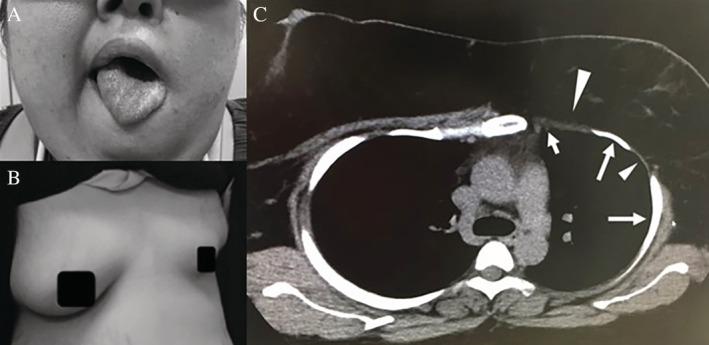

A 24-year-old woman was referred to us with daytime sleepiness. She has two congenital intractable and rare diseases, namely, Moebius syndrome and Poland syndrome. Physiological examinations and a detailed usage analysis under a ventilation device helped to conclude that hypoglossal nerve paralysis and thoracic deformity from her two underlying diseases were associated closely with her final diagnosis of obstructive sleep apnoea and sleep-related hypoventilation due to medical disorders. Bilevel positive pressure ventilation with auto-titrating expiratory positive airway pressure was effective. This is the first report that describes in detail the causal interactions between underlying two intractable and rare diseases and sleep-related breathing disorders.

一名24岁女性因日间嗜睡前来就诊。她患有两种先天性难治性罕见疾病,即默比厄斯综合征和波兰综合征。生理检查及通气设备详细使用分析表明,其两种基础疾病所致的舌下神经麻痹和胸廓畸形与最终诊断的因疾病引起的阻塞性睡眠呼吸暂停和睡眠相关通气不足密切相关。双水平正压通气结合自动调压呼气末正压通气有效。这是首份详细描述两种基础难治性罕见疾病与睡眠相关呼吸障碍之间因果关系的报告。